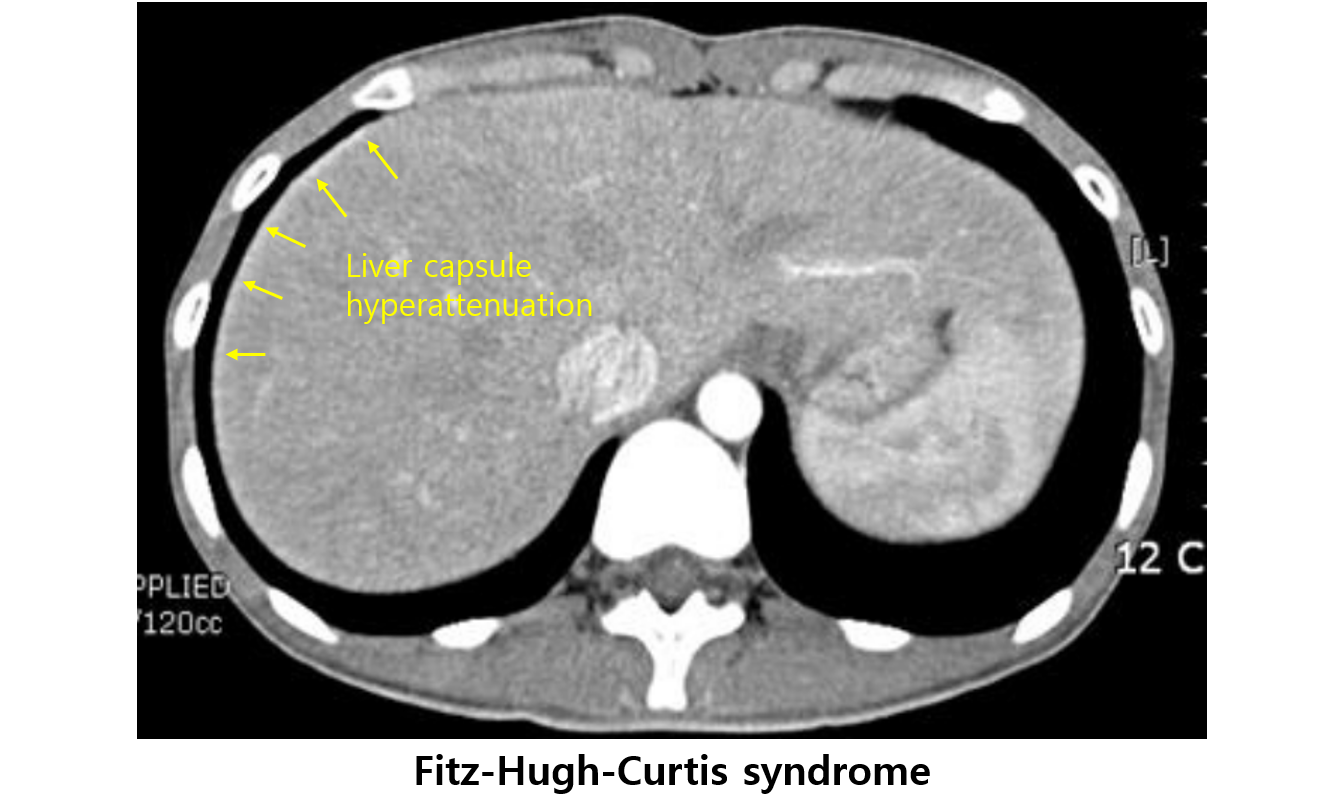

2) Fitz-Hugh-Curtis syndrome

(1) 자궁/난관의 염증이 복막을 타고 liver capsule까지 침범하여 우상복부 통증을 일으키는 현상 (= perihepatitis)

* 자궁과 난관의 내강은 막혀있지 않고 복강으로 뚫려있기 때문에 감염이 복강까지 전파될 수 있다.

(2) 임상양상: RUQ 통증, 압통/반발압통(+/+)

(3) 검사소견: CT - liver capsule hyperattenuation

(4) 치료: PID 치료와 동일